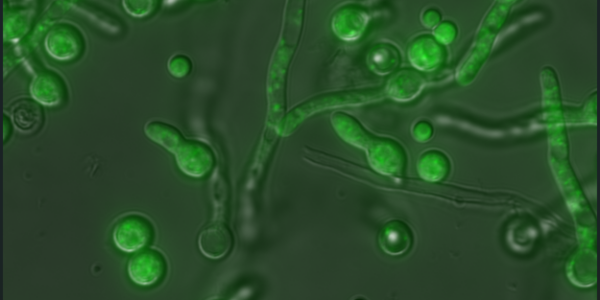

New Study Reveals How Immune Cells Help Defend Against Candida Infections

New research shows that eosinophils, immune cells usually linked to allergies, also play a protective role against Candida infections by…